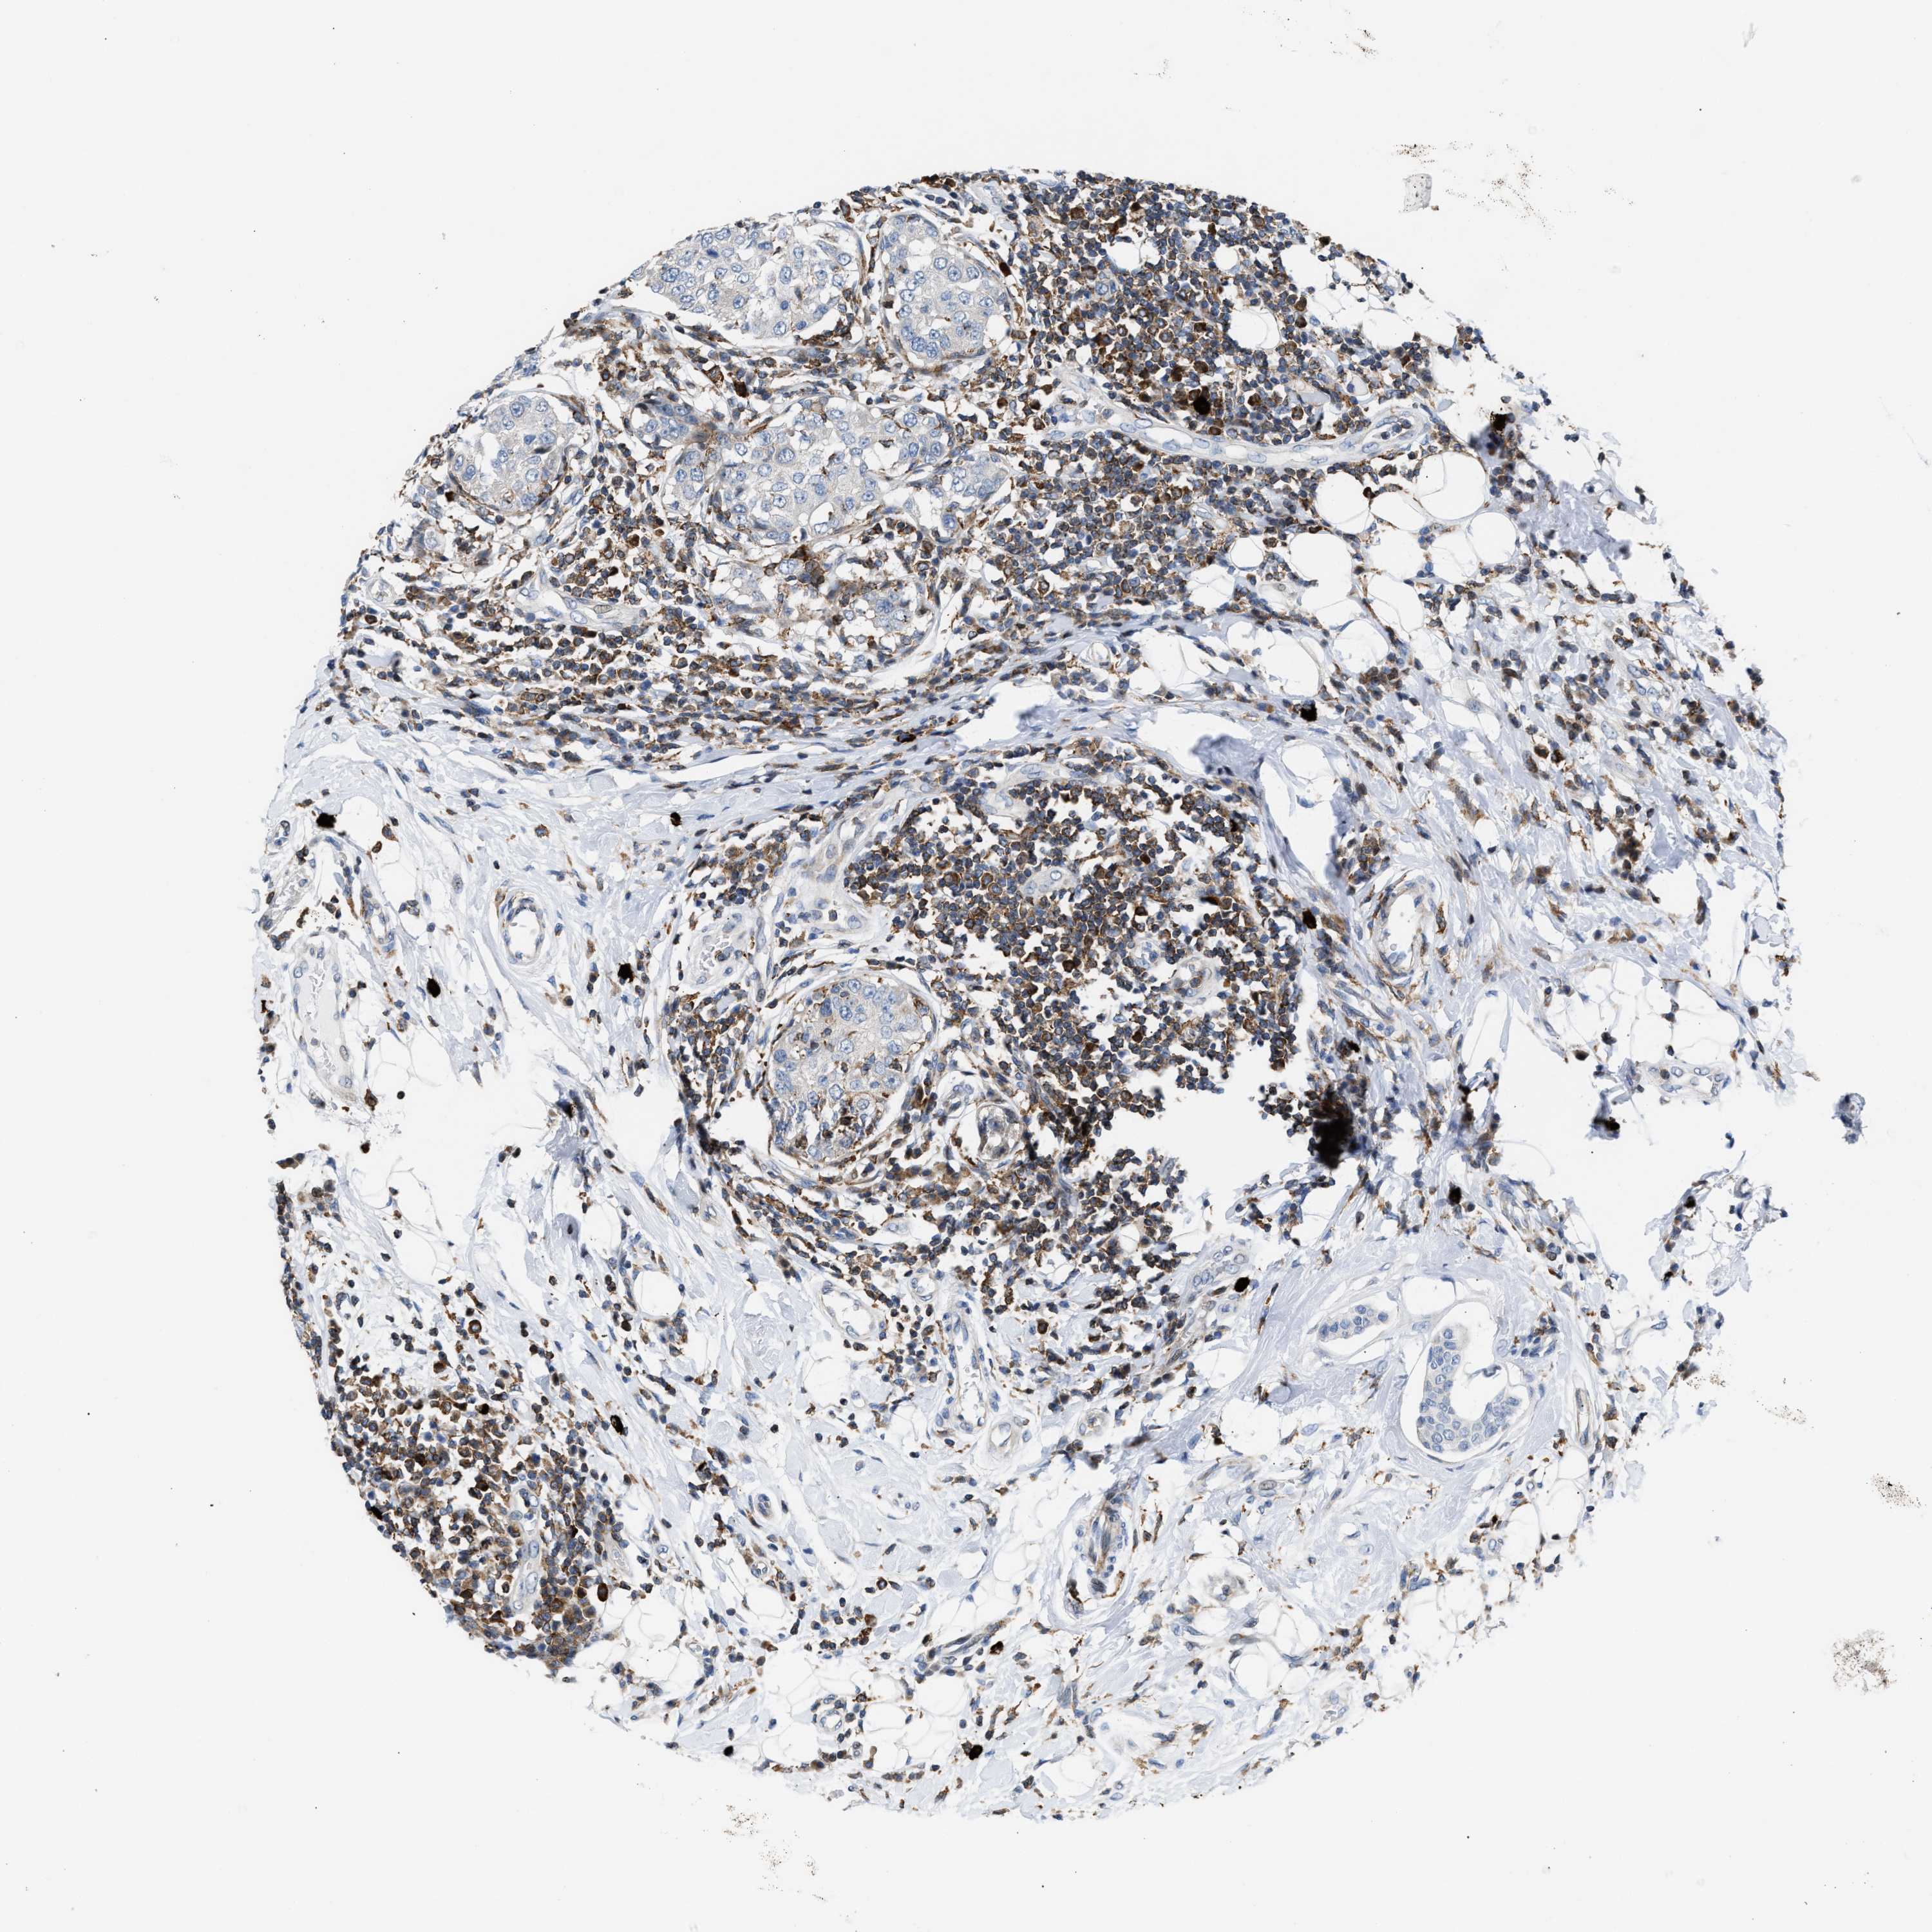

BRCA TCGA BRCA VALIDATION PROTEIN EXPRESSION